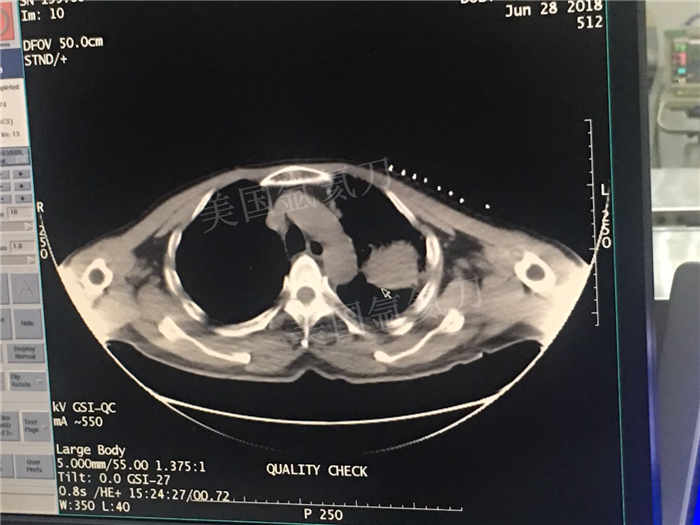

下一篇:中日友好医院氩氦刀冷冻消融治疗胸膜间皮瘤